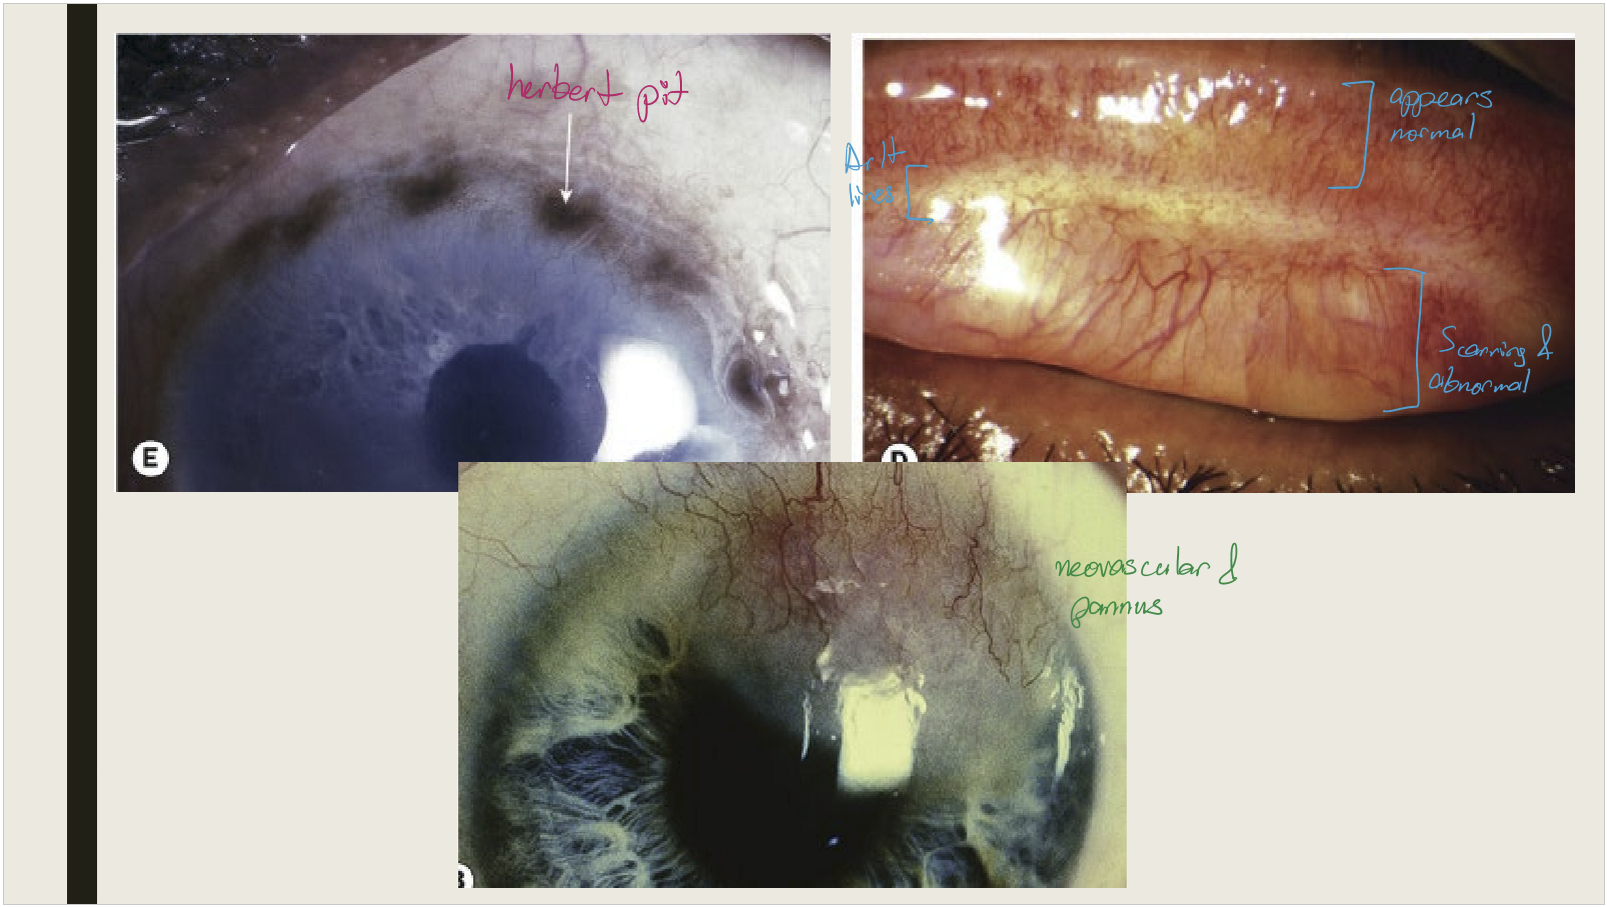

What happens to superior limbal follicles after they resolve in cicatricial trachoma?

<p>They leave shallow pits (Herbert pits)</p>

What are the corneal and eyelash changes seen in cicatricial trachoma?

<p>Corneal opacification with vascularization; trichiasis and distichiasis</p>

Mixed papillary + follicular reaction, mucopurulent discharge, superior epithelial keratitis, pannus formation

<p>Mixed papillary + follicular reaction, mucopurulent discharge, superior epithelial keratitis, pannus formation</p>

Conjunctival scarring

<p>Conjunctival scarring </p><ul><li><p>Mild infection: linear or stellate scarring</p></li><li><p>Severe infection: broad confluent scared (Arlt lines)&nbsp;</p></li><li><p>Superior tarsal effected more then other areas of conjunctiva&nbsp;</p></li></ul><p></p>